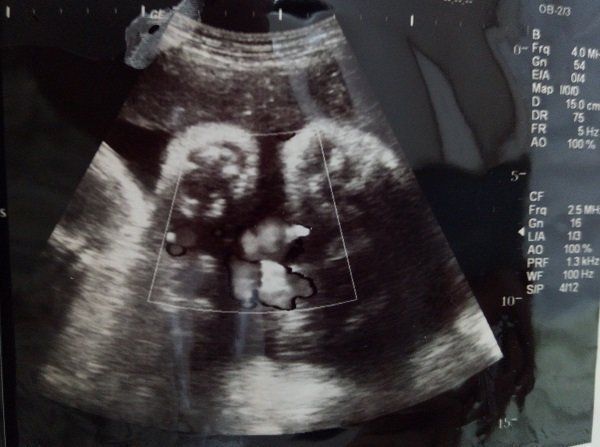

水野谷つむぎさんの妊娠39週目のエコー写真

この日が最後の検診になりました。この時点で3000gあると言われていた息子は、この2日後、ついにおなかのなかからでてきてくれました!